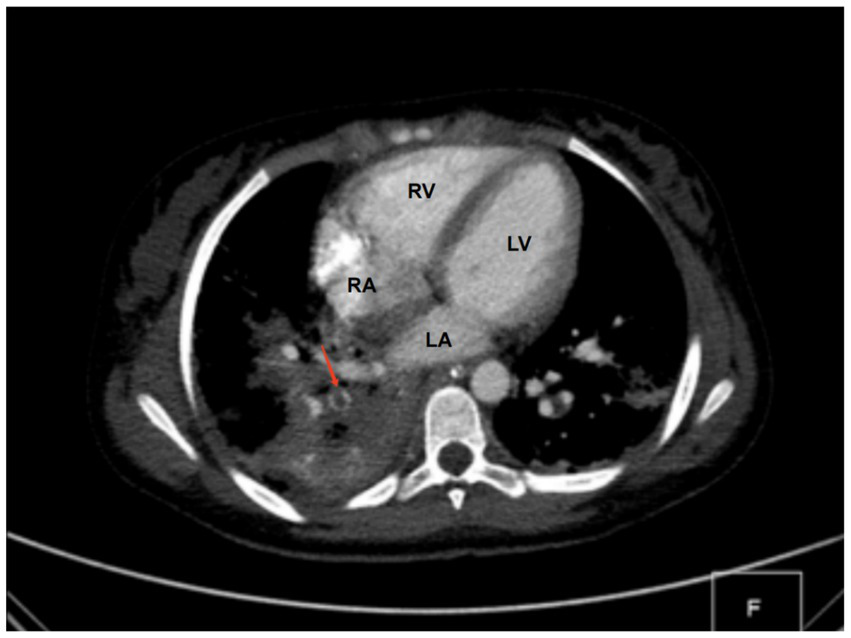

Diagnostic basis: blood routine test: white blood cell count (WBC) of 11.89 × 109 cells/L (elevated), hemoglobin (HB) level of 86 g/L (decreased), C-reactive protein (CRP) level > 256 mg/L (elevated). Procalcitonin (PCT) level: 42.33 ng/mL (elevated). Coagulation function: Fibrinogen (Fib) level of 6.64 g/L (elevated), prothrombin time (PT) of 14.6 s (prolonged), D-dimer level of 11.94 mg/L (elevated). Liver and kidney functions + electrolytes: total protein (TP) level of 48.9 g/L (decreased), albumin (ALB) level of 23.8 g/L (decreased), phosphorus (P) level of 0.8 mmol/L (decreased), and calcium (Ca) level of 2.13 mmol/L (decreased). Blood culture and sputum (collected from the bronchoalveolar lavage) culture indicated MRSA, but sensitive to vancomycin. On bilateral femoral vein color Doppler ultrasound, thrombus structures were identified in the right popliteal vein, femoral vein, and the initial segment of the right external iliac vein. Color Doppler ultrasound of the right lower limb indicated cellulitis. Chest CT and computed tomography angiography showed multiple consolidations in both lungs with scattered small cavities in the right lower lobe, and bilateral pleural effusion suggestive of infectious lesions. Pulmonary artery reconstruction displayed localized filling defects in the middle segment of the posterior basal branch (approximately 4.8 mm × 5.8 mm × 4.1 mm) (Figure 1). Similar findings were observed in some small arterial branches of the left lower lung. These findings, combined with the clinical history, suggested PE. Cardiac echocardiography revealed left ventricular enlargement, but no significant abnormalities in the posterior wall motion. The left ventricular systolic and diastolic functions were normal.

Figure 1. CT findings. A localized filling defect in the middle segment of the posterior basal branch, measuring approximately 4.8 × 5.8 × 4.1 mm (red arrow). LA, left atrium; LV, left ventricle; RA, right atrium; RV, right ventricle.